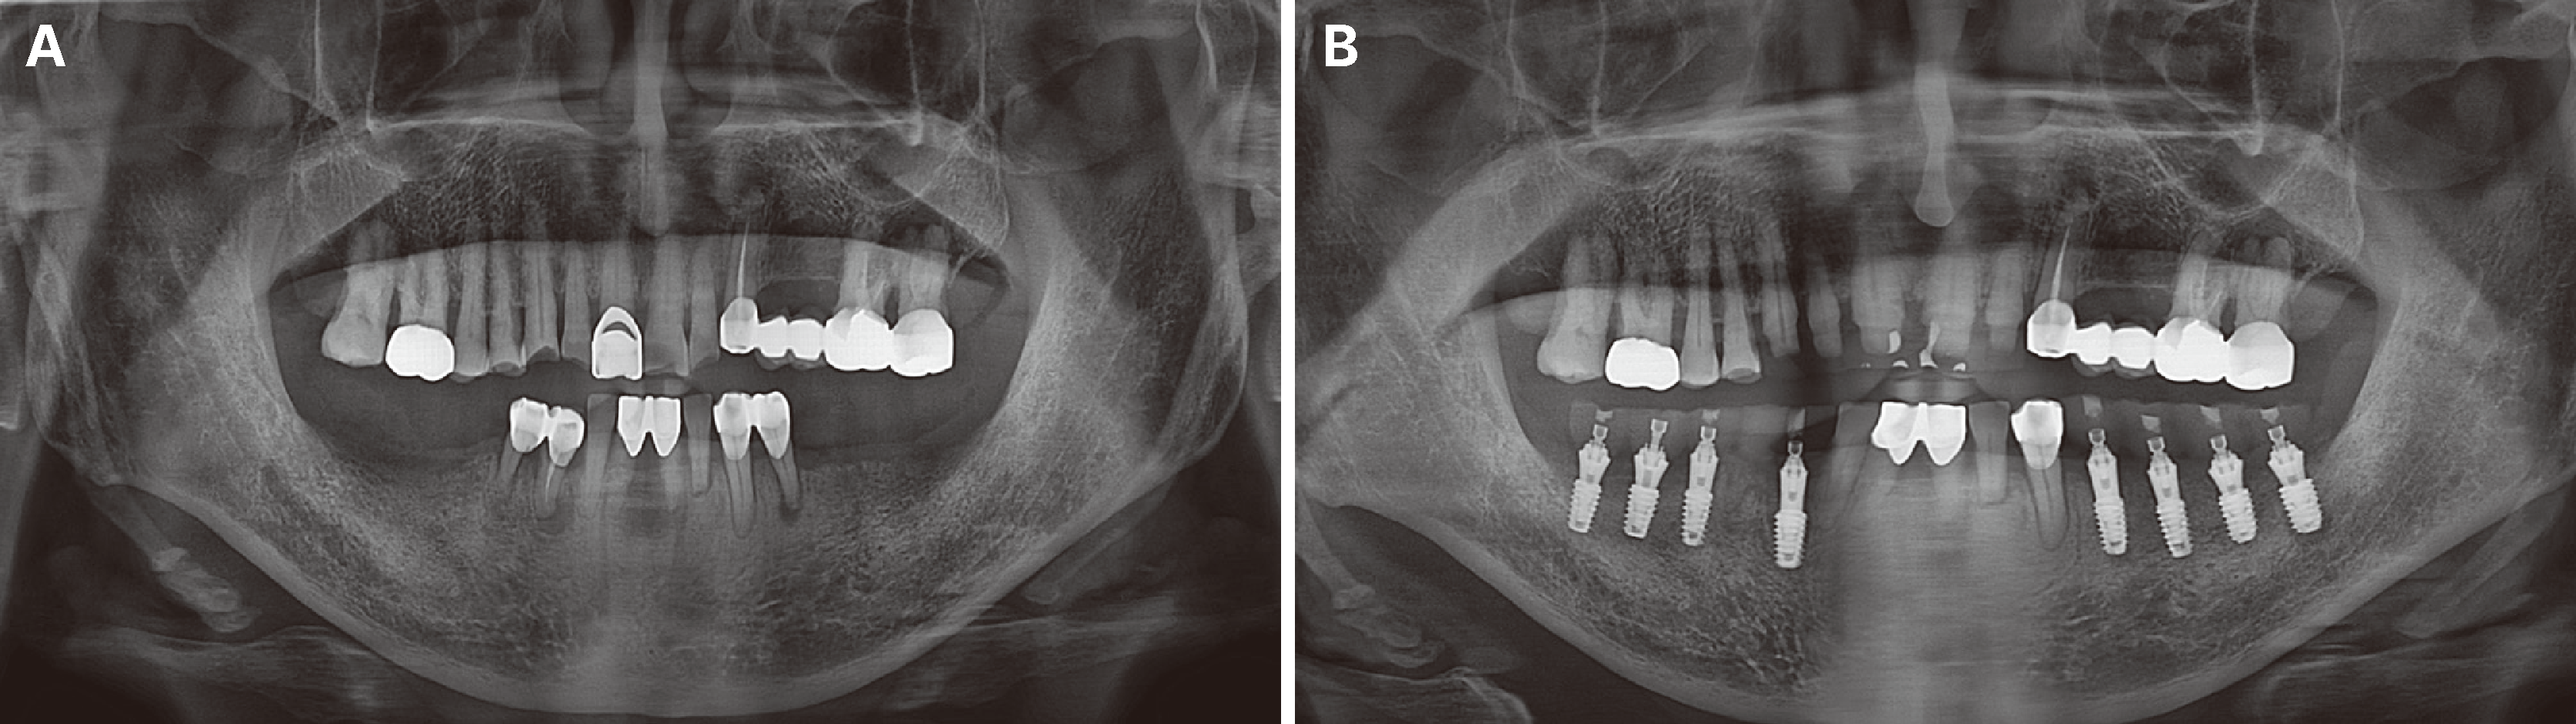

Fig. 3

(A) Initial panoramic image, (B) Panoramic image of implant placement and immediate loading on lower posterior areas.

Following confirmation of anterior end-to-end occlusion in CR, the patient underwent evaluation with CBCT, panoramic radiographs, and intraoral photographs. Rehabilitation involved zirconia full-veneer crowns for the maxillary anterior teeth (#13-22) and implant-supported fixed prostheses for the mandibular edentulous areas (#34-37, 43-47). The splinted left lower canine and premolar were separated by sectioning the distal aspect of the canine restoration, while extraction of the right lower canine (with a periapical lesion) and premolar was performed to ensure adequate posterior support. Maxillary anterior teeth were initially prepared, and occlusal adjustment of the provisional crowns established a stable anterior stop in CR at the appropriate VD.

Immediate loading of temporary implant prostheses using the Highness® system (Highness Co., Daegu, South Korea) was performed following implant placement in the bilateral mandibular posterior regions. After establishing a stable anterior bite stop with anterior restorations, implants were placed at positions #34, 35, 36, 37, 43, 45, 46, and 47, and provisional prostheses were immediately loaded.

Osstem TS III fixtures (Osstem Implant Co., Seoul, South Korea) were placed at #36 and #37, and Dentis S-Clean SQ-SL implants (Dentis Co., Daegu, South Korea) at #34, 35, 43, 45, 46, and 47. Immediately post-surgery, Highness® base abutments were connected with 30 Ncm torque, followed by attachment of Highness® scan bodies using hand torque. Digital impressions of the maxillary and mandibular dentitions, including a buccal bite scan reflecting the established anterior bite stop, were obtained using Primescan (Sirona Dental Systems GmbH, Bensheim, Germany) and analyzed with Exocad software (Exocad GmbH, Darmstadt, Germany). The following day, polymethyl methacrylate (PMMA) Highness® provisional restorations were delivered with hand torque, establishing partial group function occlusion during lateral excursions (Fig. 3, 4).